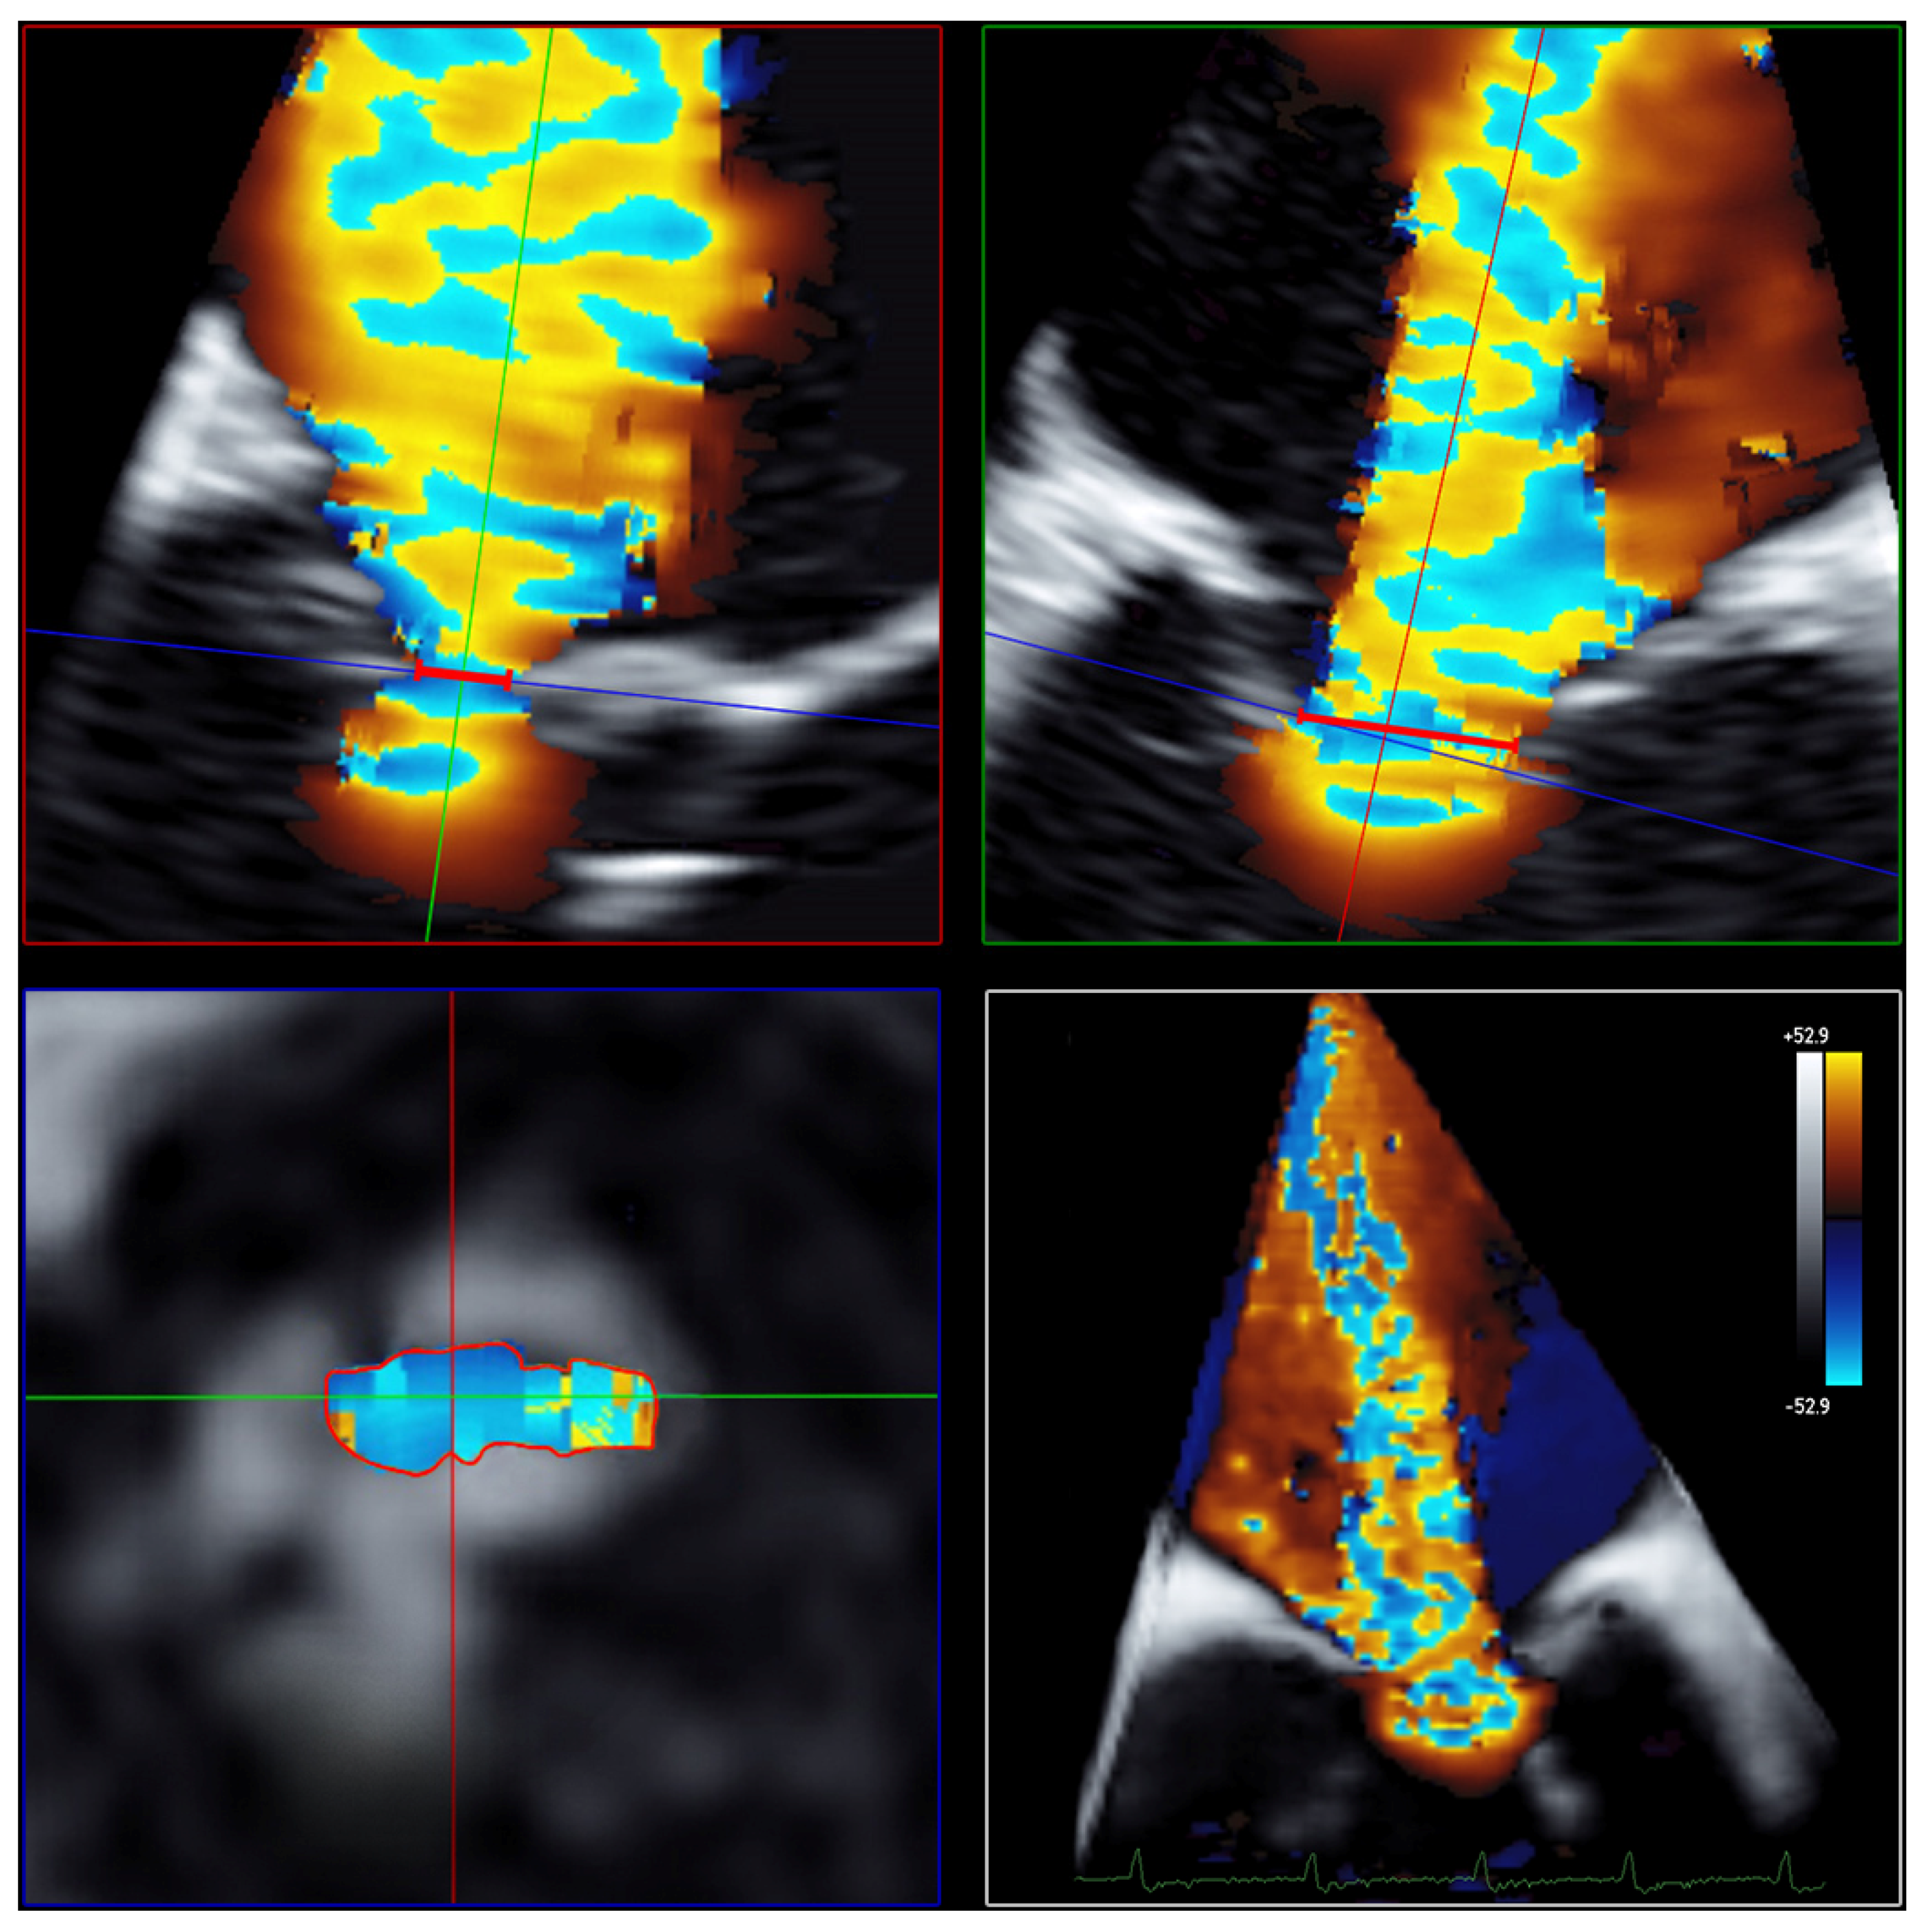

The AROA was measured by subtracting the color from the full-volume 3D color Doppler datasets. The AROA was planimetrically adjusted to the minimum cross-sectional plane of the anatomic regurgitation defect between the mitral valve leaflets (Figure 4). The area of the minimal anatomic regurgitation defect was measured by tracing the boundary of the leaflets. Analogous to the measurement of the 3D VCA, settings for brightness and contrast were fixed at 50% values and smoothening.

Figure 4. Determination of AROA using multiplanar reconstruction of the 3D color Doppler dataset without color. Echocardiographic images with 3 slice planes and 3D reconstruction (lower right) of the 3D color Doppler dataset (mid-systolic) with subtraction of color. Planimetric fitting of the 2 upper planes along the course of the color Doppler jet; third plane (lower left) adjustment orthogonal to planes along the jet. Then, subtraction of color and finding the minimum coaptation defect between the mitral valve leaflets using translation and tilting of the third plane; manual measurement of the minimum coaptation defect using outlining. Abbreviations: AROA = anatomical regurgitation orifice area; 3D = three-dimensional.